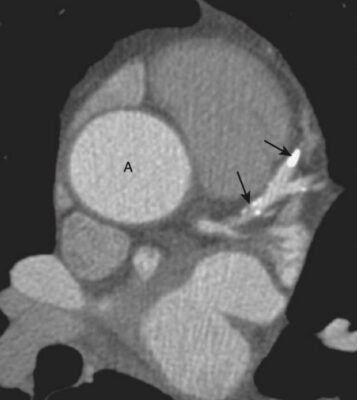

Chụp CT mạch vành (CCTA) — Giải phẫu bình thường

CCTA có độ chính xác khá tốt so với chụp động mạch vành xâm lấn (đặt thông), vẫn là tiêu chuẩn tham chiếu trong nghiên cứu động mạch vành.

Có nhiều biến thể của giải phẫu động mạch vành bình thường. Ở đây chỉ mô tả phân nhánh phổ biến nhất (Hình 12).

Hai động mạch vành chính là động mạch vành trái và phải.

- Động mạch vành trái (LCA) phát sinh từ đỉnh động mạch vành trái tại van động mạch chủ. Nó phân chia gần như cùng một lúc thành động mạch mũ và động mạch gian thất trước (nhánh xuống trước trái (LAD). LAD, sau đó tạo ra các nhánh chéo (diagonal) và các nhánh vách (septal). Động mạch mũ có các nhánh biên (marginal) (Hình 13).